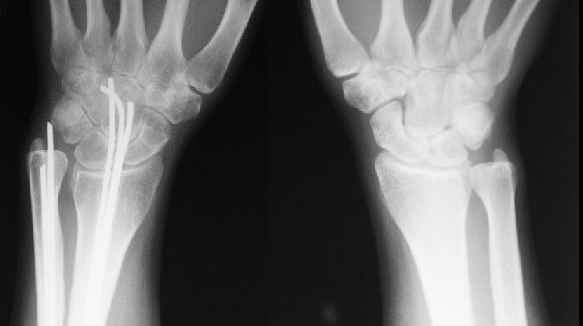

Уважаемые коллеги, Госпитализирована женщина, 31 год. Травма 26.09.06. Бытовая, упала. Оперирована в одной из горбольниц открыто, пучками спиц. 1 месяц в гипсе.

Подвижность усилилась примерно в 2 мес. (видимо, перелом спиц в лучевой кости). Движения в локтевом суставе N, ротация хорошая (подвижность лучевой кости), в кистевом тыльная 5-10 гр, ладонная 30гр. Обсуждаем варианты реостеосинтеза. Спицы удаляем все, при удалении из центрального отломка лучевой без вскрытия кости в области перелома не обойтись. Если восстановить ось и длину лучевой кости, получается дефект ~1,5-2 см. Замещать дефект удлинением одого из отломков в аппарате? Долго, и функция кисти и пальцев может еще ухудшиться.Поэтому думаем про укорачивающую резекцию обеих костей, локтевой чуть больше, остеосинтез пластинами, наверно, LCP. Блокируемый интрамедуллярный остеосинтезтоже доступен, но есть ли тут у него преимущества? Или есть смысл попытаться не трогать локтевую, а заместить дефект лучевой аутотрансплантатом из крыла? Или резецировать головку локтевой? Какие вариант и почему тут предпочтителен, на Ваш взгляд? Спасибо!Александр Виноградский клиника травматологии УНИИТО

Вряд ли получится такой дефект. Укорочение во многом связано с угловой деформацией, после устранения которой, увеличится и длина луча. Сделайте для сравнения прямую рентгенограмму л/з сустава на здоровой стороне. Варианты взаимоотношений в дистальном луче-локтевом суставе бывают разные

> Укорочение во многом связано с угловой деформацией, после устранения которой, увеличится и длина луча. Сделайте для сравнения прямую рентгенограмму л/з сустава на здоровой стороне

Помимо отсутствия физиологической кривизны лучевой кости, есть еще и рекурвация, поэтому, после устранения углов длина вряд ли увеличится.

Сравнительные снимки в приложении